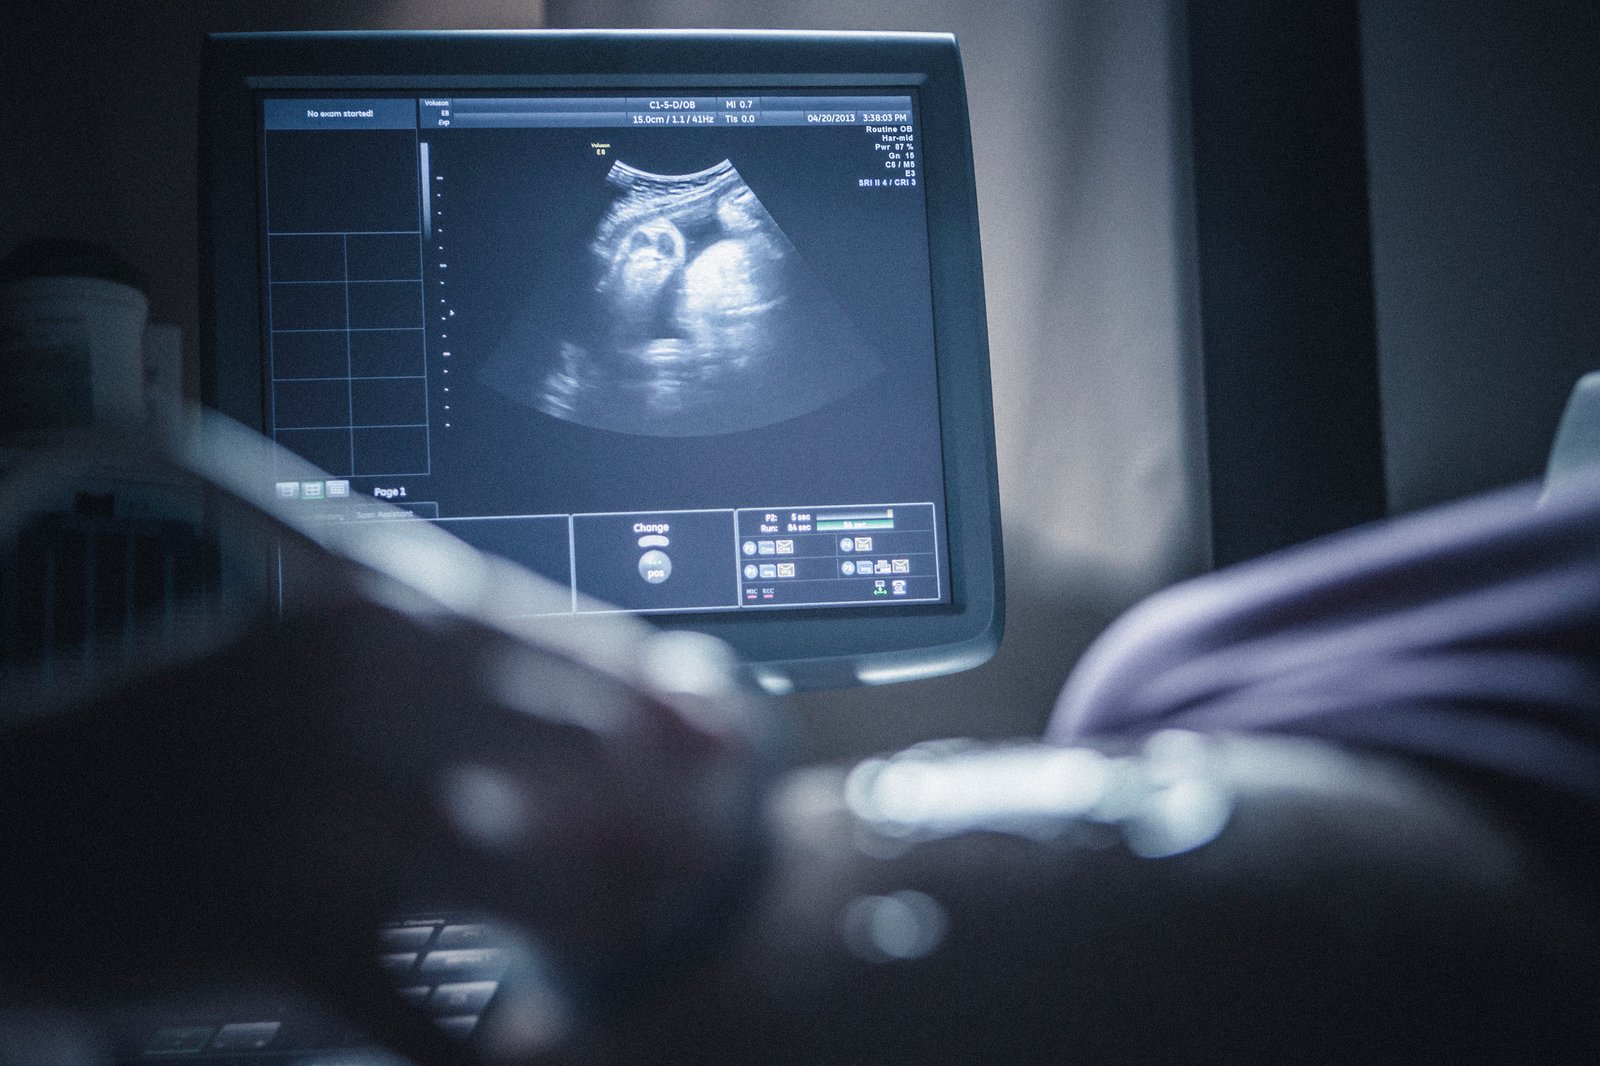

A Growth Scan, usually done during the third trimester (between 28 and 40 weeks), is a key ultrasound that helps assess your baby’s development and overall well-being during the final stage of pregnancy. It provides critical insights into how your baby is growing and helps identify any concerns that may affect delivery planning.

What to Expect During the Scan

- Performed abdominally while you lie comfortably

- Takes around 20–30 minutes

- You receive a detailed report with measurements and fetal growth chart